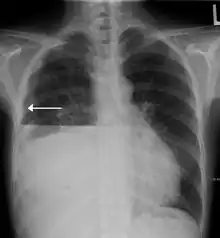

| A hydropneumothorax with a white arrow pointing to the lung's pleura | |

Hydropneumothorax is defined as the presence of both air and fluid within the pleural space.[1] An upright chest x-ray will show air fluid levels. The horizontal fluid level is usually well defined and extends across the whole length of one of the hemithorax.